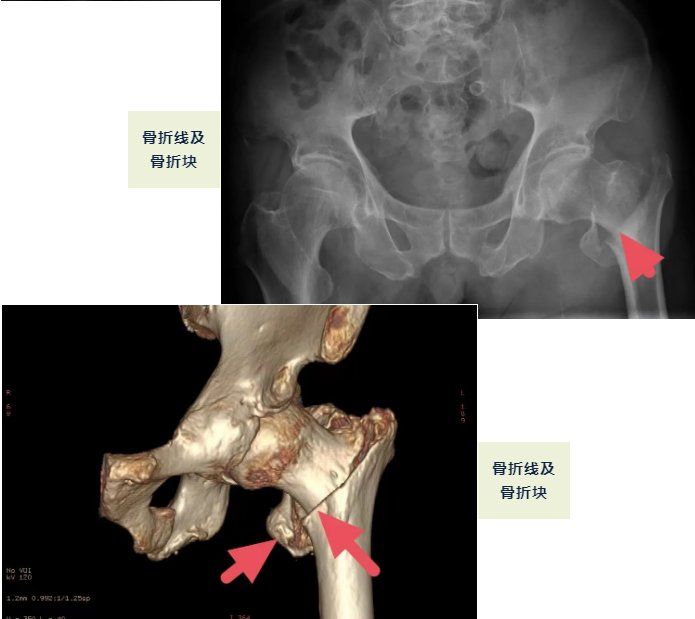

独居老人张爷爷,今年95岁,在8月31日走路时不慎滑倒,致左股骨粗隆间骨折,当晚即被家人送到我院(北京燕化医院星城院区)骨科住院治疗。

何时手术是最佳时机?肯定是越快越好!与时间赛跑,抓住48小时内的黄金期,我们骨科医护一起为老人争取。9月2日,手术如期进行,我们选择了最微创的“骨折闭合复位髓内针内固定术”,尽量减少手术的副损伤。手术9点30分开台,10点30分结束,短短1个小时时间,手术完成,张爷爷生命体征平稳,参加手术人员悬着的心终于落地。